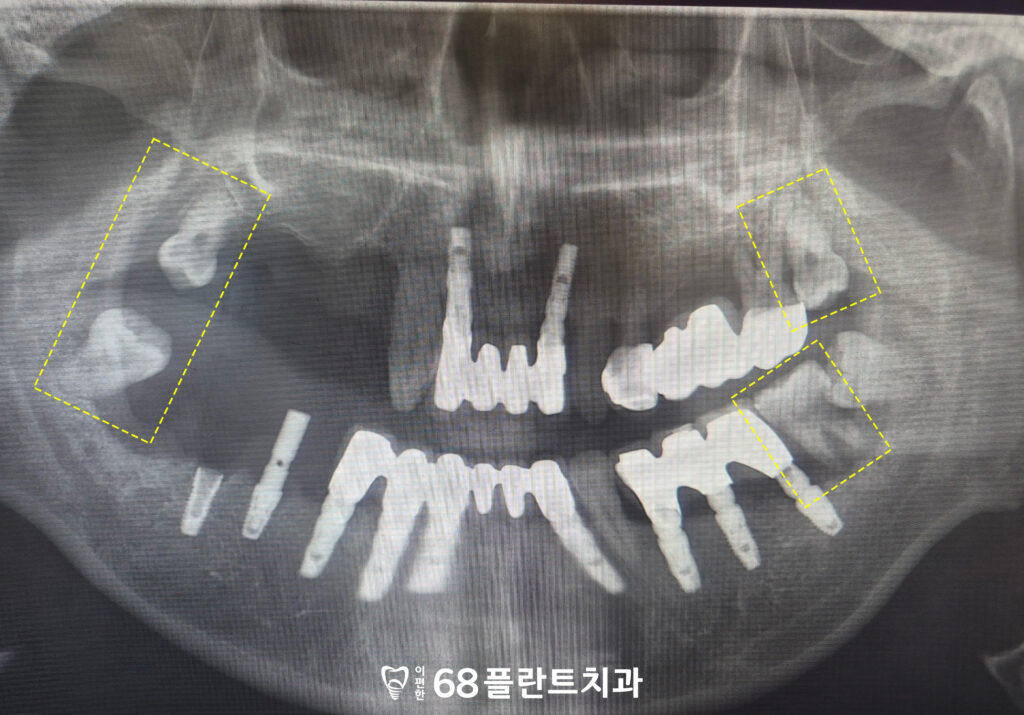

<남아있는 사랑니>

마지막으로 전체적으로 사랑니가 남아 있었으며,

왼쪽 아래는 사랑니 앞 치아 부위에

심한 골 소실이 관찰되었습니다.

이러한 치아들은 전체적인 교합에

도움을 주고 있지 않을 뿐만 아니라,

오히려 주변 치아와 잇몸 건강에

부정적인 영향을 미치고 있는 상태였습니다.

따라서 예후가 불량한 치아 및 사랑니에 대해서는

발치를 통해 구강 환경을 정리하기로 하였습니다.